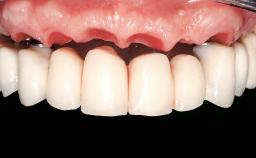

Immediate Loading of Eight Implants in the Maxilla and Six Implants in the Mandible and Final Restoration with Three-Unit and Four-Unit FDPs

Prosthesis Type FDP

Defining Characteristics Fully edentulous upper jaw to be rehabilitated with an implant-borne fixed dental prosthesis

Loading Protocol Immediate

Esthetic Risk High